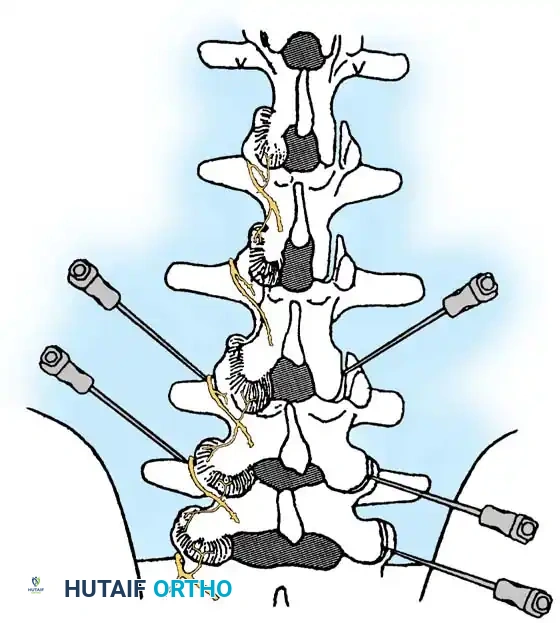

Interlaminar Approach (Technique 39-2)

The interlaminar approach is the gold standard for cervical epidural access. It is routinely performed at the C7-T1 interspace, as the epidural space is widest at this level, minimizing the risk of dural puncture or spinal cord injury. If previous posterior surgery has altered this anatomy, the C6-7 or T1-2 levels are utilized.

5. Needle Insertion: Nick the skin with an 18-gauge hypodermic needle. Under continuous AP fluoroscopic control, advance a 22-gauge, 3 ½-inch spinal needle vertically until contact is made with the upper edge of the T1 lamina, 1 to 2 mm lateral to the midline. Anesthetize the periosteum and soft tissue tract upon withdrawal.

- Tuohy Needle Advancement: Insert an 18-gauge, 3 ½-inch Tuohy epidural needle through the anesthetized tract. Advance vertically until bony contact is made with the T1 lamina.

- Loss of Resistance: Carefully "walk off" the superior edge of the lamina with the Tuohy needle, directing it anteriorly into the ligamentum flavum. Remove the stylet. Attach a 10-mL glass syringe filled halfway with air and sterile saline. Advance the needle millimeter by millimeter using continuous pressure on the plunger. A sudden "loss of resistance" indicates breaching of the ligamentum flavum and entry into the epidural space.

Transforaminal Approach (Technique 39-3)

Step-by-Step Surgical Technique:

1. Positioning: Place the patient in a modified lateral decubitus position with the symptomatic side facing up. Prepare and drape the lateral neck.

2. Fluoroscopic Orientation: Identify the target neuroforamen. Tilt the C-arm slightly caudad-to-cephalad and anterior-to-posterior to maximize the visualization of the oval neuroforamen.

3. Needle Trajectory: Insert a 25-gauge, 3 ½-inch spinal needle. Advance slowly under live fluoroscopy until contact is made with the lower aspect of the superior articular process.

* Crucial Step: You must stay strictly posterior to the foramen to avoid the vertebral artery, which runs in the anterior aspect of the foramen. Orient the needle bevel notch anteriorly to force the needle tip posteriorly during advancement.

- Foraminal Entry: Redirect the needle to "walk off" the bone into the posterior foramen by 3 to 4 mm. Do not advance further medially than the midpoint of the articular pillar on the AP view.

- Contrast Flow: Remove the stylet. Aspirate vigorously. Inject 0.5 mL of nonionic contrast under live fluoroscopy. You must observe filling of the oval neuroforamen and distal flow along the exiting nerve root. If rapid vascular washout is seen, abort the procedure immediately.

- Therapeutic Injection: Once an acceptable, non-vascular dye pattern is confirmed, slowly inject 1 mL of solution (0.5 mL of 2% preservative-free lidocaine mixed with 0.5 mL of non-particulate steroid).

Lumbar Transforaminal Epidural Steroid Injection (TFESI)

The transforaminal approach (selective nerve root block) places the medication directly at the ventral interface between the herniated disc and the inflamed nerve root.

Key Procedural Steps:

1. Oblique Fluoroscopy: The C-arm is rotated to an ipsilateral oblique angle (typically 15-25 degrees) to visualize the "Scotty Dog" anatomy. The target is the "safe triangle" located just inferior to the pedicle (the "eye" of the Scotty Dog) and superior to the exiting nerve root.

2. Needle Placement: A 22-gauge or 25-gauge spinal needle is advanced down the beam of the fluoroscope until the tip rests in the 6 o'clock position relative to the pedicle.

3. Lateral Confirmation: The C-arm is rotated to a true lateral view to ensure the needle tip is in the superior-anterior aspect of the neuroforamen, avoiding dural puncture medially.

- Contrast Injection: Live fluoroscopy during contrast injection must demonstrate medial flow into the epidural space and lateral flow outlining the exiting spinal nerve.